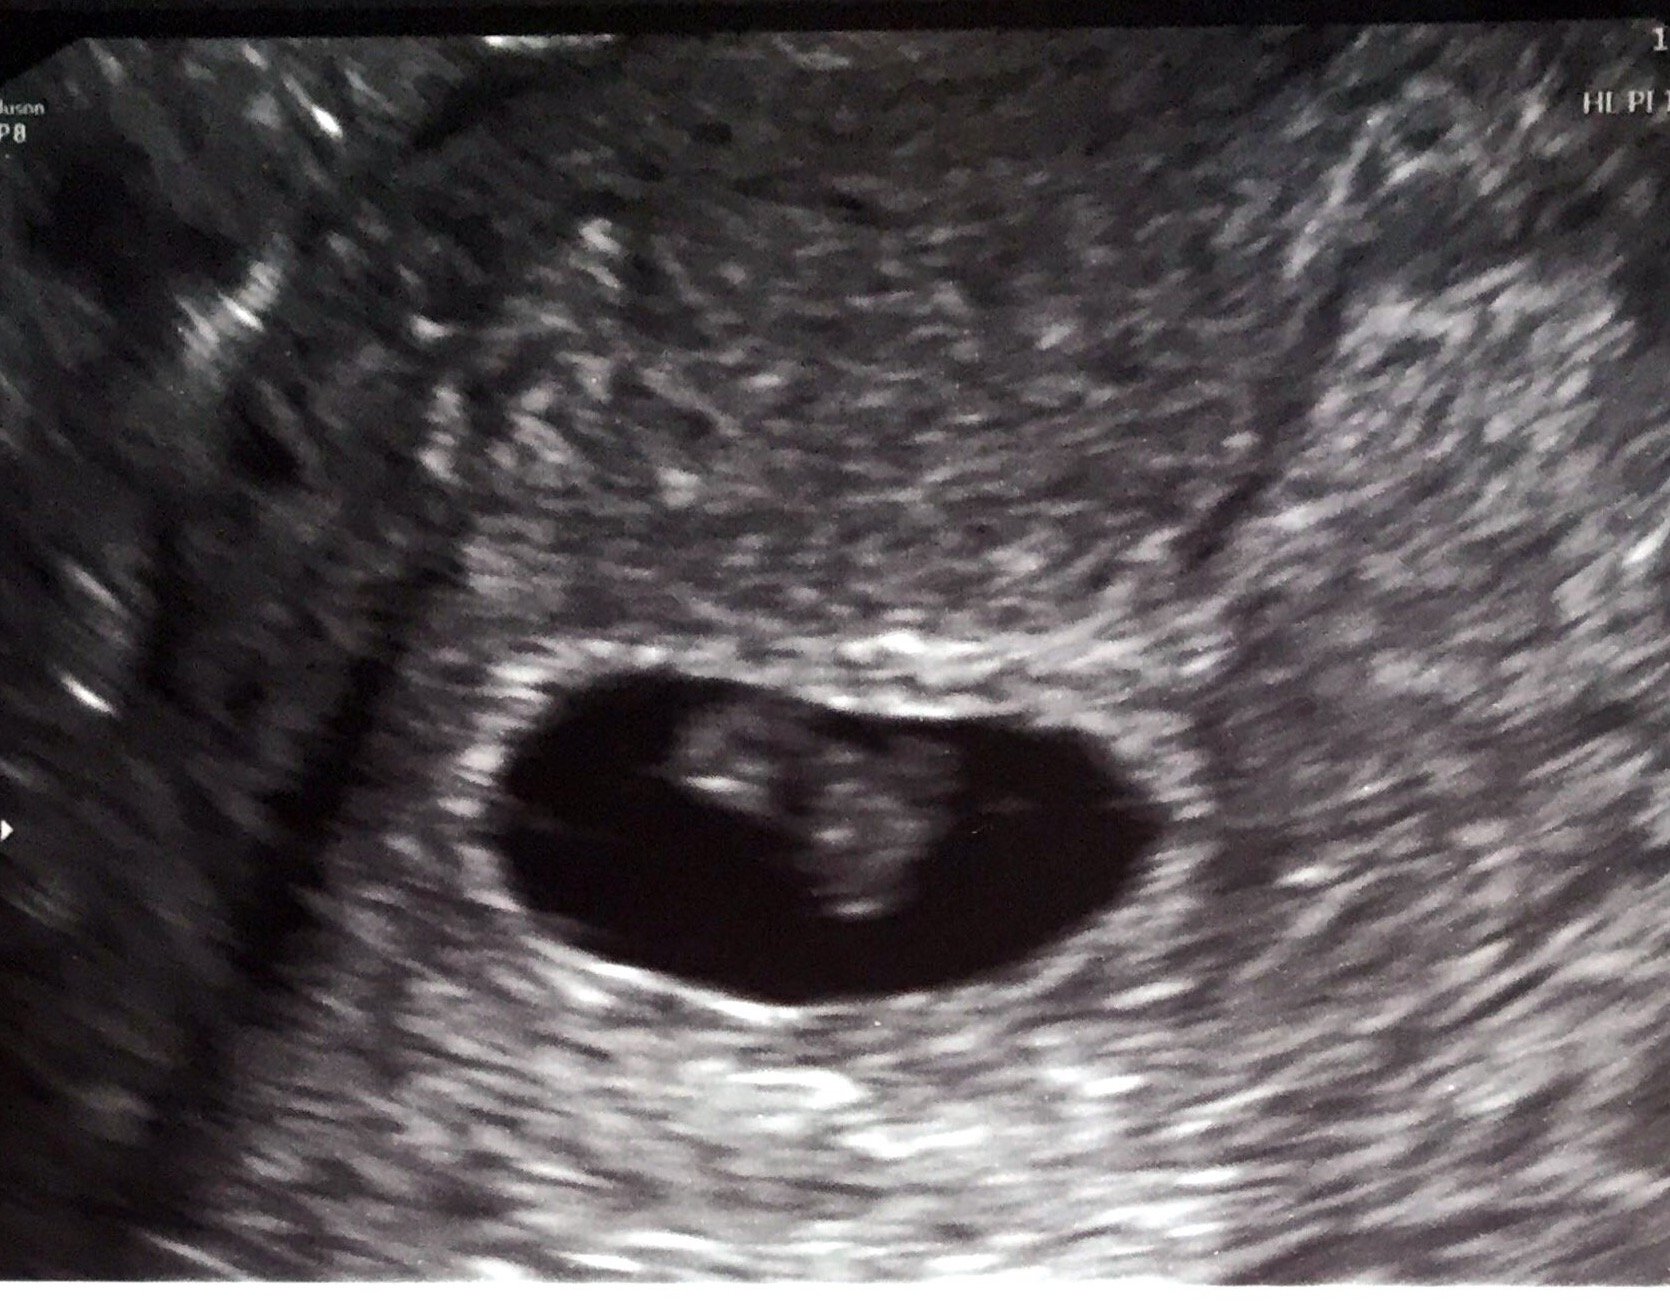

Our tiny one! 7 weeks 5 days. Measuring right on track with a HB of 163. LO was moving around a ton, which seemed to surprise the tech. But DD was exactly the same, so I'm not surprised at all. My official due date is now 12/31, but I hope you ladies don't mind if I stay here in January with you!